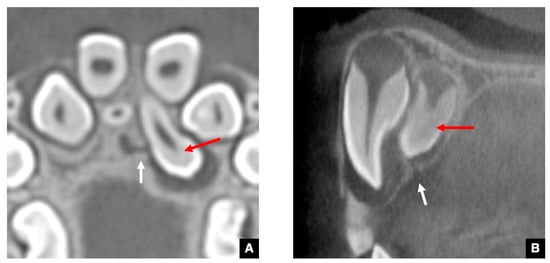

2.3. CT Images of GT in Maxillary Anterior Teeth with Delayed Eruption and Mesiodens